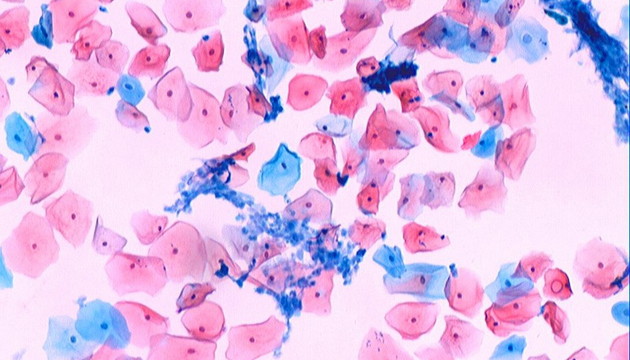

病理學(xué)按觀(guān)測(cè)對(duì)象分器官、組織、分子病理學(xué)。器官病理學(xué)依賴(lài)肉眼及顯微鏡,確定病變性質(zhì)。組織病理學(xué)則通過(guò)切片染色觀(guān)察細(xì)微病變,常用HE、PAS、革蘭氏、巴氏及油紅O染色。分子病理學(xué)分析蛋白或基因表達(dá),用于疾病進(jìn)程與藥效評(píng)估,常用IHC免疫組化定蛋白質(zhì),F(xiàn)ISH技術(shù)檢測(cè)特定基因片段,助力精準(zhǔn)醫(yī)療。

免疫組化病理,明美ML51-M搭配MSX2拍攝